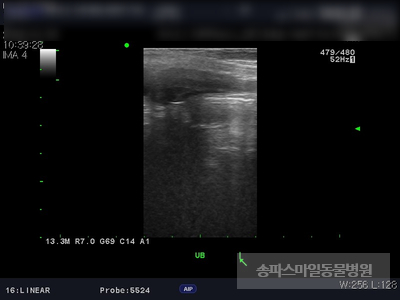

초음파 검사상 자궁의 크기가 매우 확장되었으며 자궁 내부의 액체가 고여있는 것으로 확인되었습니다.

강아지 자궁축농증이 진단되었습니다.